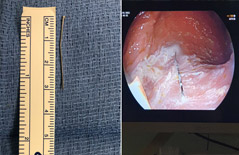

وصلت هذا الأسبوع الى المركز الطبي "تسافون"- بوريا ، طفلة عربية ، تبلغ من العمر 4 سنوات وقد ابتلعت (دبوس) مشبكاً وجدته على الأرض في منزلها.

وقال د. أفي أون مدير معهد الجاسترو (منظار الأمعاء) في المركز الطبي:" في حالات مثل هذه يجب علينا كطاقم طبي العمل في أسرع وقت ممكن لاستخراج الجسم الغريب الذي ابتلعه الطفل قبل ان يدخل الى المعدة، حيث استطعنا استخراجه بعملية تمت بمساعدة المنظار قبل ان يُحدث أي اضرار من شأنه ان يتطلب عملية جراحية معقدة. ان المشبك يعتبر جسما حادا وطويلا من شأنه ان يؤدي الى ثقب في الجهاز الهضمي ولحالة مرضية معقدة".

وأضاف د. أون:" هناك أهمية قصوى للتوقيت في اخراج هذا الجسم الغريب والحاد قبل ان يدخل في المعدة، والاثني عشر، حيث بالإمكان استخراجه من خلال المنظار الذي يتم إدخاله من خلال أنبوب مرن من فتحة الفم واستخراج الجسم الغريب بواسطة الحلقة المثبتة في نهايته، وهذا ما حصل فعلا حيث خضعت الطفلة لهذه العملية وتم استخراج الجسم الغريب ، وفي اليوم التالي تم تحريرها الى المنزل".